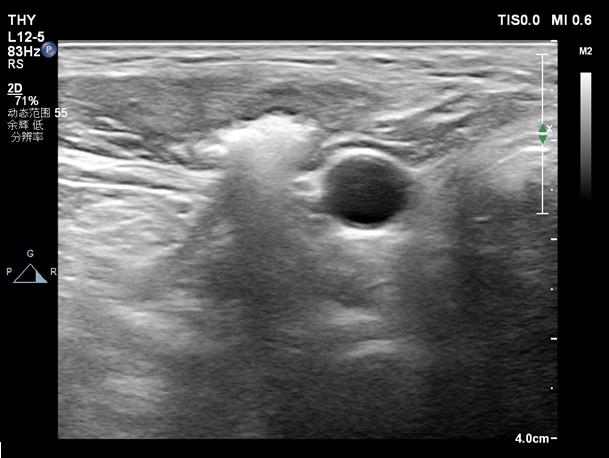

今年上半年,患者因肾功能不全及泌尿系感染入住我院肾脏内科,吴永贵主任医师为病人做了精心检查,发现颈部术区任可见多处甲状旁腺组织,考虑甲状旁腺瘤复发,这是一系列疾病的根源,必须要铲除。但患者做过两次手术,全身情况又差,已不适合再次手术,病人一天天不停的忍受着煎熬,吴永贵看在眼里,急在心里。此时,超声科正好开展了超声引导下甲状腺结节微波消融技术,吴永贵知道后,眼前一亮,主意有了,何不在超声引导下对颈部病灶进行定点消融呢。于是,他与超声科陈永超主任医师取得联系,陈永超对病人进行了详细检查。该病人情况的确相当复杂,原来四个甲状旁腺切除区域均重新长了腺瘤,手术切口下移植灶也起了结节,超声引导下消融相当困难,对介入超声消融技术要求极高。

于是两个科室联合制定了周密计划,术前、术后病人观察、血PTH及血钙检测、术后处理由肾脏内科负责,消融手术由陈永超精细操作,通过两次消融手术,将上述五个病灶灭活,患者血PTH从术前1200多降到100多,血钙也降至正常,并持续四个月没有反弹,患者全身症状明显改善,术后第二天就说了句“好久没睡上这么一个安稳觉了”。